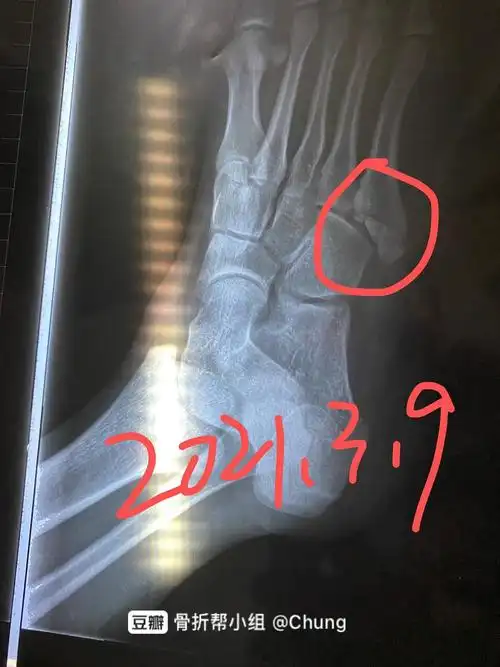

右脚第五跖骨基底部骨折